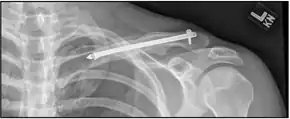

![]() | |

| X-ray of a left clavicle fracture | |